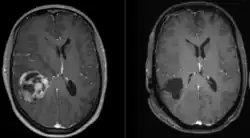

_im_MRI_preoperativ_und_postoperativ.png)

Die neurochirurgische Operation mit Verminderung der Hauptmasse des Tumors (Tumorreduktion) kann das Fortschreiten der Erkrankung verlangsamen, aber nicht dauerhaft verhindern, da praktisch immer einzelne Tumorzellen das gesunde Gehirngewebe schon infiltrativ durchwandert haben und deswegen eine vollständige Tumorentfernung nicht möglich ist. Der Eingriff kann stereotaktisch oder offen durchgeführt werden.[16][23]

Ob ein chirurgischer Eingriff möglich ist, hängt von der Lokalisation des Tumors und dem Allgemeinzustand des Patienten ab. Eine möglichst vollständige Entfernung ist mit längerem Überleben assoziiert.[16][23]